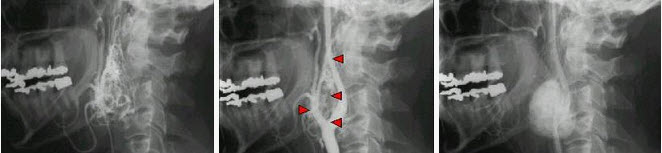

男,24岁,颈部疼痛,并右上肢麻木,以手部明显,请根据所提供图像,选择最可能的诊断()。

A.(颈4~5)神经鞘瘤

B.(颈4~5)脊膜瘤

C.(颈4~5)海绵状血管瘤

D.(颈4~5)血管母细胞瘤

E.(颈4~5)胶质瘤